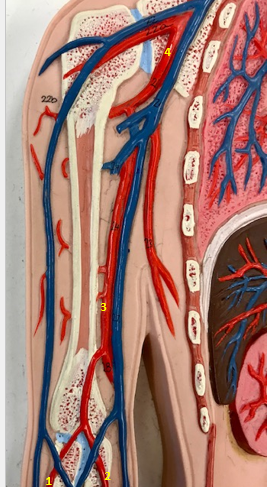

Tunica intima

Name the blue arrow

Lines lumen and release vasoactive chemicals

Function of tunica intima

Venous valves

Name the pink arrow

Prevent backflow of blood

Function of venous valves

Tunica media

Name green arrow

Vasoconstriction and vasodilation

Function of tunica media

Tunica externa

Name the purple arrow

Anchor and bind vessel

Function of tunica externa